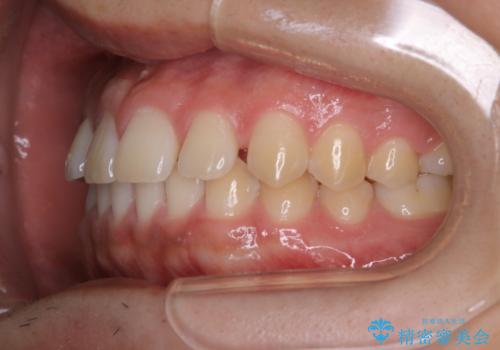

- 上のすきっ歯が気になるとご相談にいらした方です。上下顎ともにスペースがあったため、インビザラインFULLにて見た目と噛み合わせの改善も同時に行いました。

元々は上前歯のみの部分矯正をご希望されていましたが、下の歯もスペースがあり、噛み合わせ的にも上のみの部分治療は難しいことをお話ししました。前歯のみの部分矯正を行った場合、前歯の隙間だけが閉じて奥歯が噛めなくなってしまう場合もあります。インビザラインFULLにて治療することで、噛み合わせと見た目を同時に改善させることができ、大変喜んでいただけました。